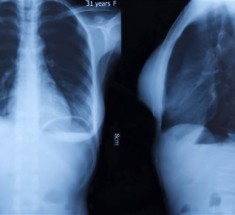

Des radiothérapies ciblées et moins nocives pour les cellules saines ? Telles sont les perspectives ouvertes par les résultats obtenus par des chercheurs français du Laboratoire de chimie physique – matière et rayonnement (CNRS/UPMC), en collaboration avec des scientifiques allemands et américains (1). En effet, jusqu’à présent, la radiothérapie employée dans la lutte contre le cancer, utilise une large gamme d’énergie en irradiant les tissus biologiques.

La radiothérapie actuellement utilisée dans près de 50 % des traitements du cancer irradie les tissus biologiques avec un rayonnement situé sur une large gamme d’énergie afin de détruire les cellules cancéreuses. Les travaux de cette équipe internationale menée par deux chercheurs du CNRS, du Laboratoire de chimie physique – matière et rayonnement (CNRS/UPMC) devraient permettre en ciblant plus finement la gamme d’énergie utilisée d’améliorer la précision et la qualité du traitement. Leurs recherches fondamentales à l’origine visaient à étudier le comportement de la matière à l’échelle atomique soumise à un rayonnement, ici de type rayon X, dont l’énergie est choisie de manière très précise. Lorsqu’un atome absorbe des rayons X d’une énergie donnée, un processus, appelé « relaxation coulombienne interatomique », se met en œuvre, provoquant l’émission d’électrons par un des atomes au sein d’une molécule. Dans leur expérimentation, les chercheurs ont montré qu’il est possible de produire une quantité importante d’électrons de basse énergie dans l’environnement immédiat de cet atome cible. On parle alors de phénomène de résonance.

L’irradiation de tissus biologiques en radiothérapie se faisant sur une large gamme d’énergie, l’avantage d’utiliser une radiation d’énergie finement choisie afin de provoquer une émission résonante des électrons est double: les rayons X pénètrent profondément dans les tissus mais seuls des atomes précis au sein de de molécules choisies, administrées préalablement de façon à cibler les cellules cancéreuses sont ainsi excités, et les tissus sains plus éloignés ne sont pas affectés par l’irradiation. De plus, l’excitation résonante est dix fois plus efficace que l’excitation non résonante produite par une irradiation moins spécifique. La dose totale d’irradiation peut ainsi être considérablement réduite.